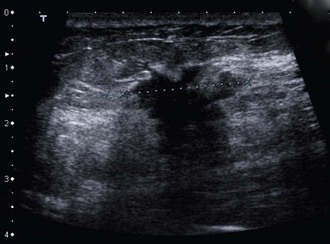

Ultrasound has long been used to distinguish solid lesions from cysts and has a specificity of 100% for this. Modern B-mode ultrasound demonstrates breast anatomy in great detail and is complementary to mammography. Benign lesions can be distinguished from malignancy with a sensitivity for cancer of at least 85%. Ultrasound can accurately measure the size of a cancer (Fig. 45.7) and can guide percutaneous needle biopsies and cyst aspiration (Fig. 45.8).